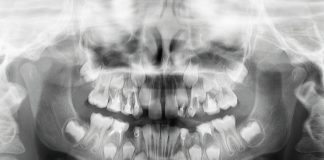

Dopo un follow-up di 4 anni, l’impianto appare perfettamente stabile e osteointegrato, la riabilitazione è ben tollerata dal paziente e, sia a livello clinico che radiografico, non sono presenti alterazioni né meccaniche né biologiche. Non si evidenziano segni di patologia perimplantare o di riassorbimento della cresta (figura 10,11).

Controllo intraorale a 4 anni.